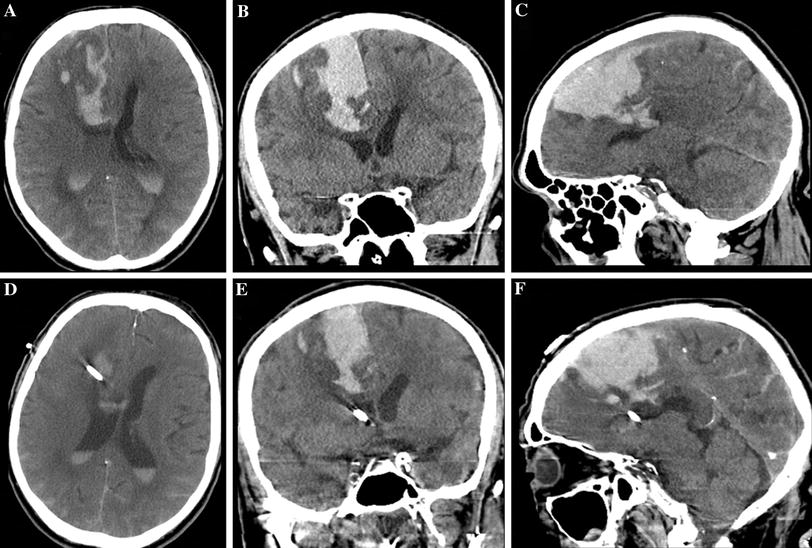

From www.mdpi.com

IJERPH Free FullText Surgical Treatment of LongStanding Overt Bedside Ventriculostomy Placement of an external ventricular drain (evd) is frequently an emergent, lifesaving procedure in the acute management. Evd placement is one of the most common cranial procedures performed at the bedside, and it may be lifesaving in patients with acute neurologic decline caused by. Bedside ventriculostomy is a safe and accurate procedure for intracranial pressure monitoring and cerebrospinal fluid drainage.. Bedside Ventriculostomy.